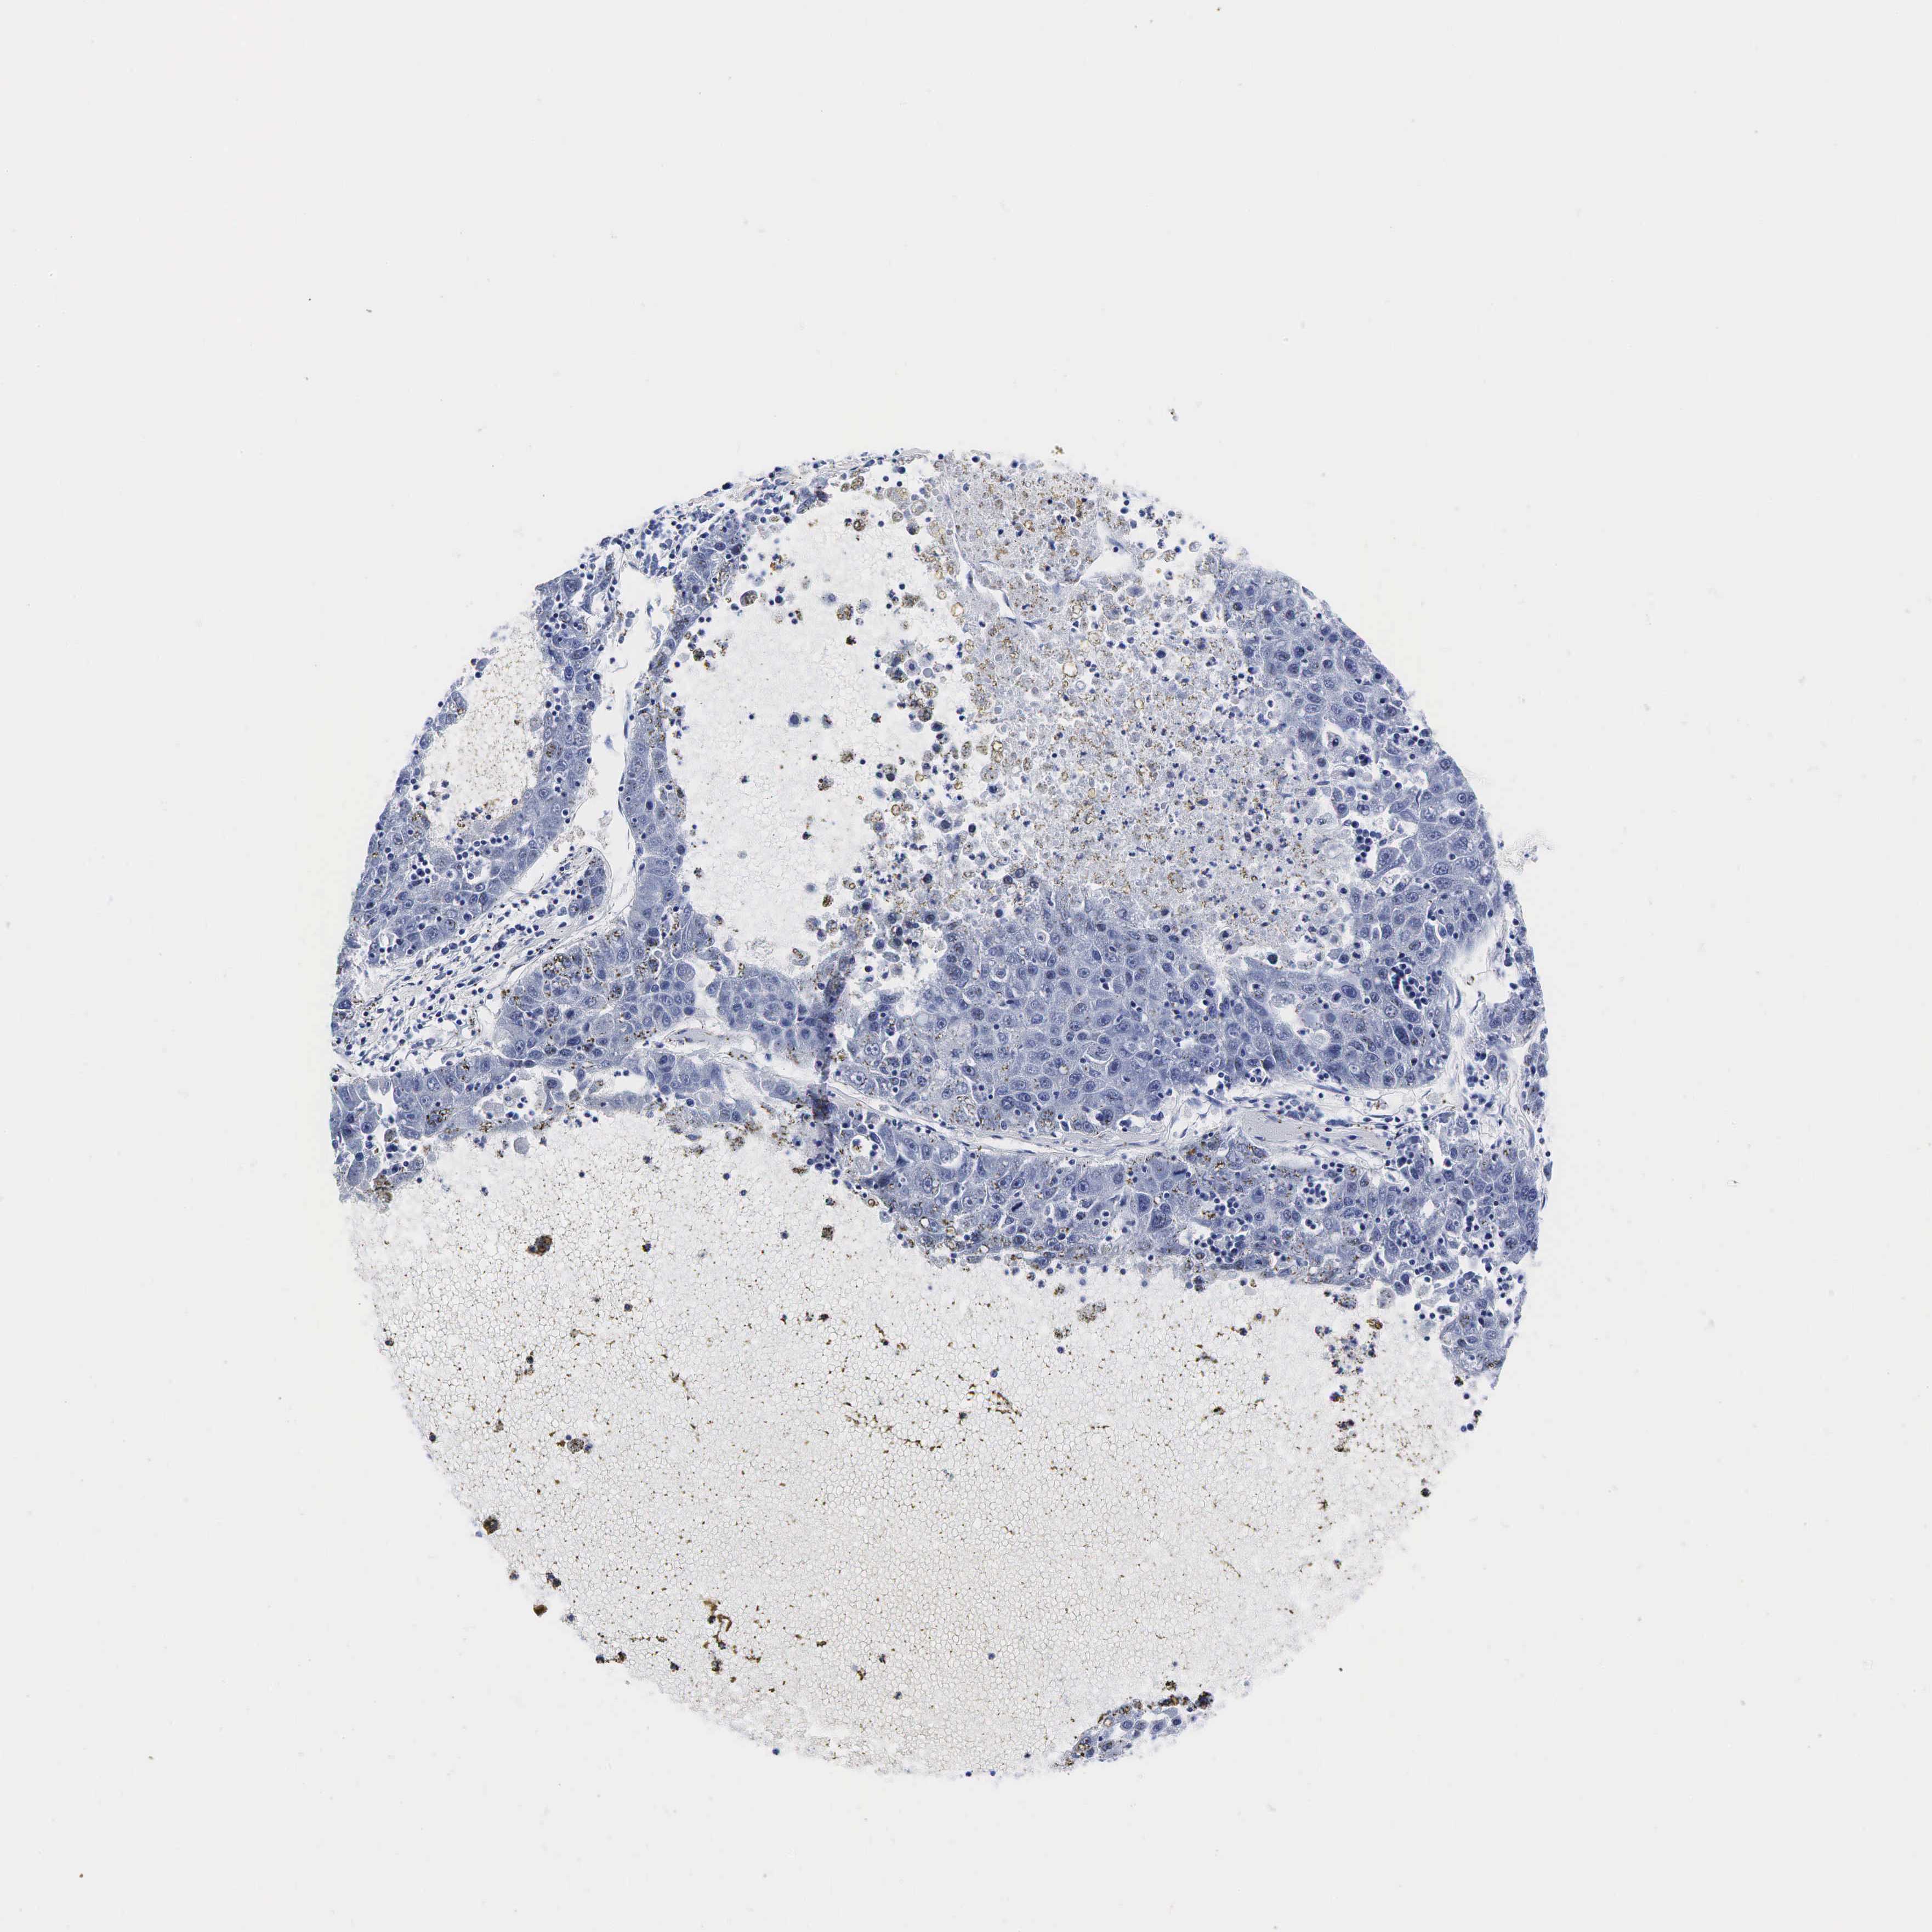

LIVER CANCER - Protein expressioni

A mouse-over function shows sample information and annotation data. Click on an image to view it in a full screen mode. Samples can be filtered based on level of antibody staining by selecting one or several of the following categories: high, medium, low and not detected. The assay and annotation is described here.

Note that samples used for immunohistochemistry by the Human Protein Atlas do not correspond to samples in the TCGA dataset.

Antibody stainingi

Antibody staining in the annotated cell types in the current human tissue is reported as not detected, low, medium, or high, based on conventional immunohistochemistry profiling in selected tissues. This score is based on the combination of the staining intensity and fraction of stained cells.

Each image is clickable and will lead to virtual microscopy that enables deeper exploration of all samples and also displays staining intensity scores, fraction scores and subcellular localization as well as patient and tissue information for each sample.

Antibody HPA002740

Antibody CAB000077

Antibody CAB056155

Staining

High

Medium

Low

Not detected

Intensity

Strong

Moderate

Weak

Negative

Quantity

>75%

75%-25%

<25%

None

Location

Nuclear

Cytoplasmic/membranous

Cytoplasmic/membranous,nuclear

Carcinoma, Hepatocellular, NOS

Cholangiocarcinoma

Carcinoma, metastatic, NOS